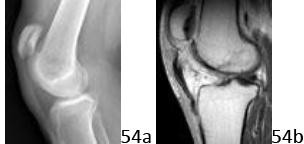

54a 54b A 28-year-old man reports an episode of buckling and giving-way of his right knee. Figure 54a and 54b show a radiograph and sagittal MRI scan. What is the most likely diagnosis?

DISCUSSION: The radiograph shows patella alta consistent with a rupture of the patellar tendon. The MRI scan confirms disruption of the patellar tendon from the inferior pole of the patella. The cruciate ligaments are not visualized in this image, and would not result in patella alta. Quadriceps tendon rupture would result in patella baja. There is no evidence of meniscal tearing on these images. The Preferred Response to Question # 54 is 4.